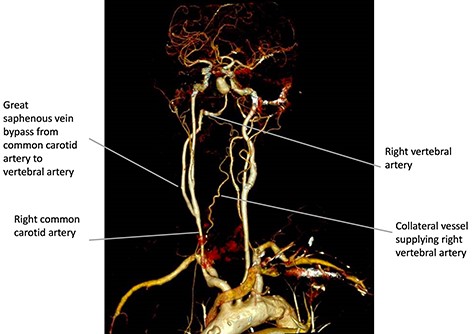

To allow endovascular access to the aneurysm, the patient underwent a right CCVAB. The procedure was performed under general anaesthetic with nasotracheal intubation. The mid portion of the right common carotid artery (CCA) was exposed in the neck above the omohyoid muscle via a longitudinal incision anterior to the medial border of the sternocleidomastoid. The incision was extended cranially and posteriorly to behind the ear and the extradural V3 segment of the vertebral artery was exposed between the transverse processes of C1 and C2. The long saphenous vein was harvested from the left thigh, reversed and after systemic heparinization, anastomosed in an end to side fashion to the CCA and to the vertebral artery. A contrast enhanced computed tomography scan confirmed patency of the graft on the Day 1 post procedure (Fig. 2). In the early post-operative period, the patient had ongoing hypotension that was likely secondary to cerebral autoregulation of blood pressure post CCVAB. The patient had also suffered from a line sepsis, which delayed the second stage of the operation.

Three-dimensional reconstruction of the contrast enhanced computed tomography scan performed on Day 1 post CCVAB, demonstrating a patent bypass and flow through the right vertebral artery and to the aneurysm.